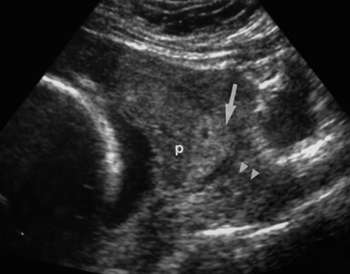

Η χαμηλή πρόσφυση του πλακούντα παρουσιάζεται σε 1:250-300 κυήσεις. Κατατάσσεται

σε προδρομικό, επιχείλιο και παραχείλιο πλακούντα (εικόνα 3). Παράγοντες κινδύνου

για την εμφάνισή του αποτελούν η μεγάλη ηλικία, οι προηγούμενες καισαρικές τομές

ή άλλες ουλές στη μήτρα, οι πολύδυμες κυήσεις και το ιστορικό τεχνητών εκτρώσεων.(3)

Χαμηλή πρόσφυση μπορεί να παρατηρείται έως και στο 25% των υπερηχογραφημάτων

που γίνονται στις 18 εβδομάδες της κύησης. Η απουσία του υπερηχογραφικού αυτού

ευρήματος σε μεταγενέστερο στάδιο της κύησης οφείλεται ίσως στη διάταση του

κατώτερου τμήματος της μήτρας. Το υπερηχογραφικό εύρημα του προδρομικού πλακούντα

κατά το δεύτερο τρίμηνο, είναι πιο πιθανό να ανταποκρίνεται στην πραγματική

θέση του πλακούντα που διαπιστώνεται κατά το τέλος της κύησης.(4) Ο κίνδυνος

επανεμφάνισης σε επόμενη κύηση μπορεί να είναι δεκαπλάσιος από ό,τι σε πληθυσμό

μαρτύρων. Το διακοιλιακό υπερηχογράφημα πρέπει να γίνεται με μέτρια διάταση

της ουροδόχου κύστης.(5) Η υπερβολική διάταση της κύστης μπορεί να προκαλέσει

μετατόπιση του πρόσθιου και οπίσθιου τοιχώματος της μήτρας, με αποτέλεσμα να

απεικονίζεται πιο ψηλά το έσω τραχηλικό στόμιο και να μην είναι σαφές το ύψος

της πρόσφυσης του πλακούντα. Το διακολπικό υπερηχογράφημα έχει μεγαλύτερη ακρίβεια

και εκτελείται όταν η διακοιλιακή εξέταση δεν είναι ικανοποιητική.(5)

Εικόνα 3. Χαμηλή πρόσφυση

του πλακούντα και θρόμβος (p= χείλος του πλακούντα, μεγάλο βέλος= θρόμβος, μικρά

βέλη= ενδοτράχηλος).